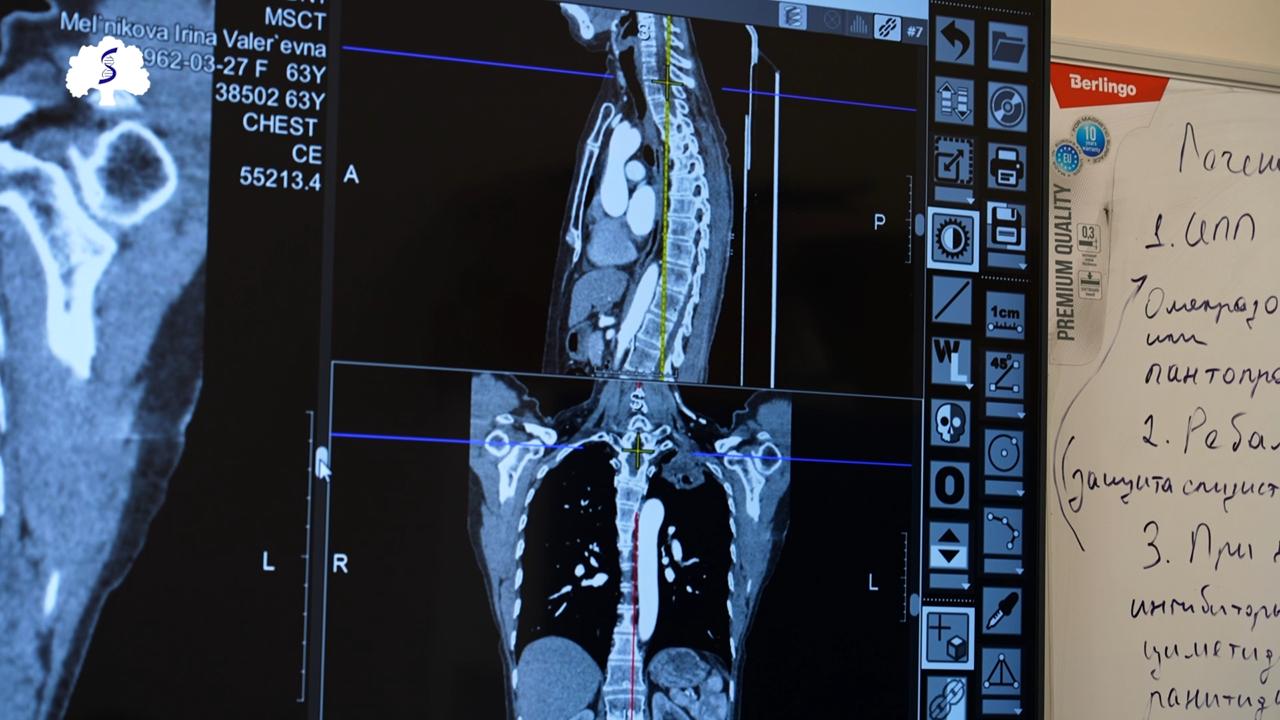

Молодая женщина пришла к врачу с, казалось бы, обычной жалобой. Рентген — как при пневмонии. Но КТ и ПЭТ-КТ показали куда более серьёзную картину — редкий и один из самых агрессивных видов рака лёгкого, рак Панкоста.

Опухоль уже затронула нервы, сосуды и ребро. За дело взялась мультидисциплинарная команда Сеченовского Университета — торакальные и сердечно-сосудистые хирурги.

Операция была большой и сложной: удалили часть лёгкого, участок грудной стенки и ребро, подключались специалисты по кардиоангиологии.